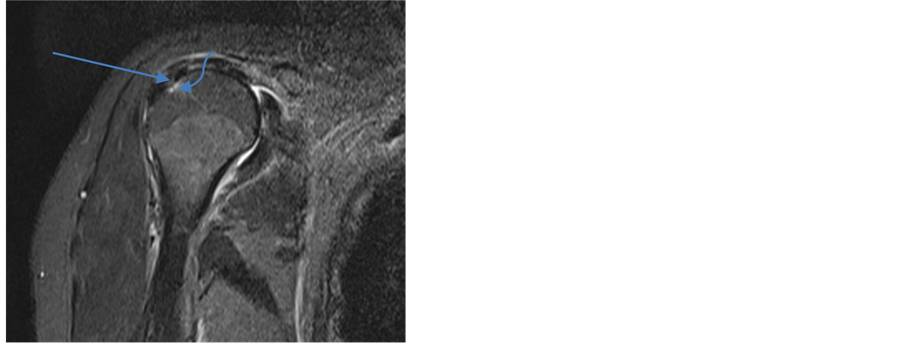

Recognized classification were used for the diagnosis of types of RCT and to categorize them for statistical calculation [4] [14] - [16] . Two MRI images have been shown to show partial thickness tear (PTT) and full thickness tear (FTT) in Figure 1 and Figure 2.

Figure 1. Coronal T2 weighted fat-suppression: MRI appearance of partial thickness tear (arrow) at the insertion of supraspinatus tendon. Also humeral head edema (curved arrow) and shoulder joint effusion can be seen.